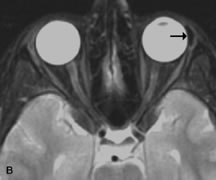

Inflammatory and Lymphoproliferative Lesions

Inflammatory conditions of the orbit, both idiopathic (inflammatory pseudotumor) and those of known causes, have been found to be hypointense to fat and isointense to muscle on Tl-weighted studies and isointense or slightly hyperintense to fat on T2-weighted images (Fig. 21).50,64,69 The more fibrous or sclerosing varieties have less signal intensity on T2-weighted images. Marked enhancement is seen in pseudotumor infiltrates after gadolinium administration.70 The same signal characteristics are demonstrated in patients with Tolosa-Hunt syndrome, with mass lesions seen in the cavernous sinuses and orbital apices.71

Fig. 21. A. T1-weighted MR scan demonstrates diffuse enlargement of both the superior rectus and levator palpebrae superioris muscles (single arrows). The involvement of the tendinous insertions and preseptal soft tissues (open arrows) as well as lack of involvement of other muscles helps differentiate this entity from thyroid-associated orbitopathy. B and C. Postcontrast fat-suppressed T1-weighted MR scans demonstrate extensive enhancement of the involved muscles as well as the preseptal (open arrows) and perinuscular tissues (double arrows).